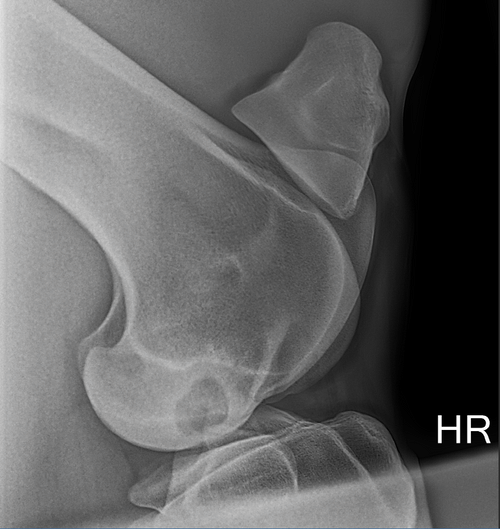

Knochenchirurgie: Die wissenschaftlichen Erkenntnisse im Bereich der Knochenchirurgie entwickeln sich rasant weiter. Unsere erfahrenen Chirurgen sind immer „up to date“ um die beste Versorgung ihres Pferdes zu gewährleisten. Dazu gehören Behandlungen von Frakturen, Zysten, Erkrankungen des Knochenmarks und Gelenkversteifungen. Frakturen oder Fissuren können durch Schrauben und Platten in die richtige Position gebracht werden. Bei Griffelbeinfrakturen werden die frakturierten Teile entfernt. Zysten werden mit synthetischem Kalziumphosphat gefüllt und/oder mit Schrauben stabilisiert. Bei einem Knochenmarködem kann nach erfolgloser konservativer Therapie der Knochen angebohrt werden (Osteostixis) und entweder mit regenerativer Medizin (z.B. Stammzellen) oder mit einer Schraube gefüllt werden.Wenn sich eine Gelenksarthrose im fortgeschrittenen Stadium befindet und die konservative Therapie nicht mehr anspricht, wird das Gelenk mittels Implantaten versteift, damit das Pferd sich ohne Schmerzen bewegen kann.